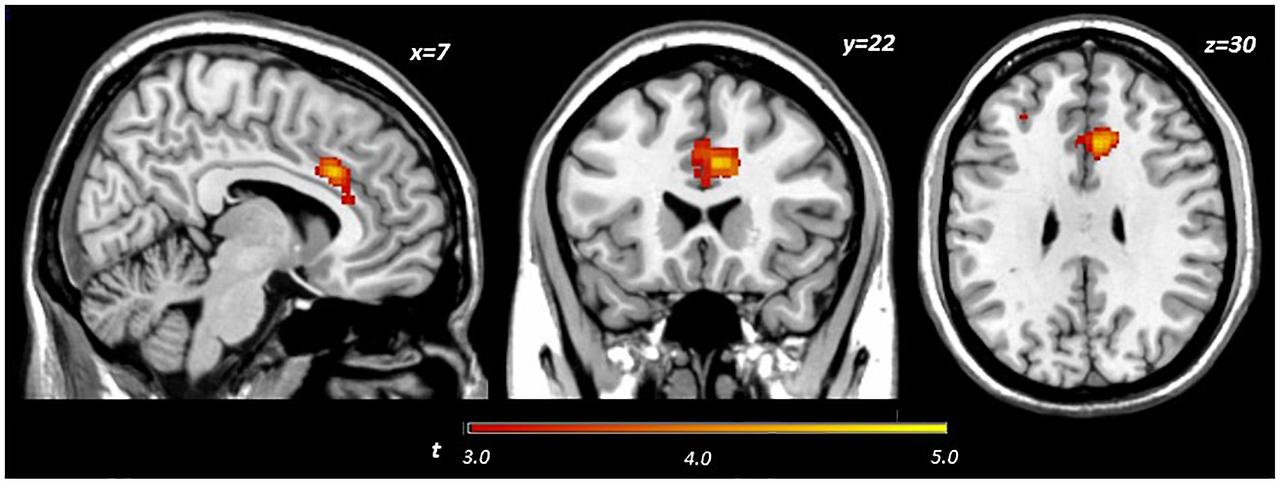

인간을 대상으로 한 연구에서도 유사한 결과가 보고되고 있습니다. Darcey et al.(2019)은 청소년을 대상으로 한 연구에서 오메가3 섭취가 낮은 그룹은 전전두엽 피질의 기능적 효율성이 떨어지고, 충동 억제력이 감소하는 경향을 보였다고 밝혔습니다. 이 연구는 fMRI를 활용해 전두엽의 활성 패턴을 관찰했는데, 오메가3가 부족한 경우 전두엽이 과도하게 활성화되면서도 실제 인지 수행 능력은 떨어졌습니다. 이는 전두엽 기능의 비효율성과 연관된 것으로 해석되었습니다. 또한 McNamara et al.(2010)은 청소년의 혈중 오메가3 수치와 주의력, 충동 억제력 간의 상관관계를 밝혀, 섭취 부족이 행동 문제와 직접 연결될 수 있음을 제시했습니다.